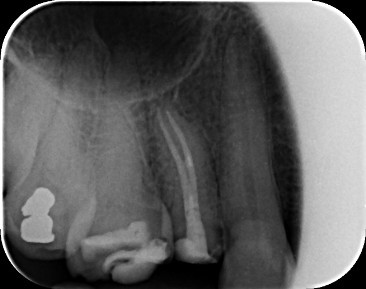

Case 1: Root Canal Treatment UR5